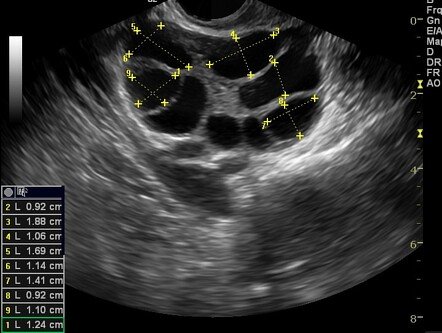

Follicular monitoring is the process of performing serial ultrasound scans to track the growth and development of ovarian follicles. It helps identify the maturation status of eggs and document the pathway to ovulation.

• Follicles are measured in 2D or 3D through ultrasound.

• Once the follicle reaches about 16 mm, it grows approximately 2 mm per day.

• When the follicle size reaches 19–20 mm, an HCG injection is given to trigger ovulation.